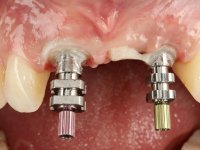

In the initial phase, it was proposed to the patient to perform the surgical implant exposure and after clinical evaluation, make prosthetic decisions. Once the healing screw was placed and the soft tissues were healed, an inadequate position of the implant was found. In view of the dramatic situation, the patient was proposed to remove the implant and put a new one after tissue regeneration. This proposal was rejected by the patient, who suggested temporary rehabilitation of the current implant. A new proposal was then made, to rehabilitate the implant, consisting of a screwed abutment, and on this, the placement of an acrylic crown with coronal and gingival components. After 6 years with the provisional treatment, the patient appeared in consultation with an abscess in tooth 1.1. After clinical and imaging analysis, it was decided to remove teeth 1.1 and 2.2, submerge the implant, place two implants at the site of 1.1 and 2.2 and perform adequate tissue regeneration. Temporization would be done with a provisional 3-element bridge, adhered with a net to the neighboring teeth. After osseointegration, definitive rehabilitation would be done with a 3-element bridge, including zirconia infrastructure and ceramic cover.

The surgical implant exposure and the healing screw placement proved to be a negative surprise regarding its position. Since the proposed removal of the implant was refused, we advanced to its provisional rehabilitation. An open tray impression technique was done, and a screwed abutment with a coronal and gingival component and an acrylic crown were made in the laboratory, using these two components. The provisional crown was placed in the mouth until a final decision was made. Six years passed before the patient returned to the clinic with an abscess on tooth 1.1. The choice to remove teeth 1.1 and 2.2 was made, to create a provisional 3-element bridge with a net to be adhered to the adjacent teeth. Surgery was planned and performed, placing the two implants at the site of 1.1 and 2.2, and the implant at the 2.1 site was cut with the objective of submerging it, while adequate tissue regeneration was performed (Surgical Work performed By Dr. Manuel Neves). During osseointegration, the patient used the fixed provisional bridge. A first impression was made for confection of a zirconia screwed provisional bridge, which worked the soft tissues for twelve weeks. The definitive impression was made with the individualisation of custom impression copings. Final rehabilitation was done with ceramized abutments, and also a bridge with zirconia infrastructure and ceramic cover. Due to the inclination of the implant placed at the site of tooth 1.1, the bridge required cemented fixation.